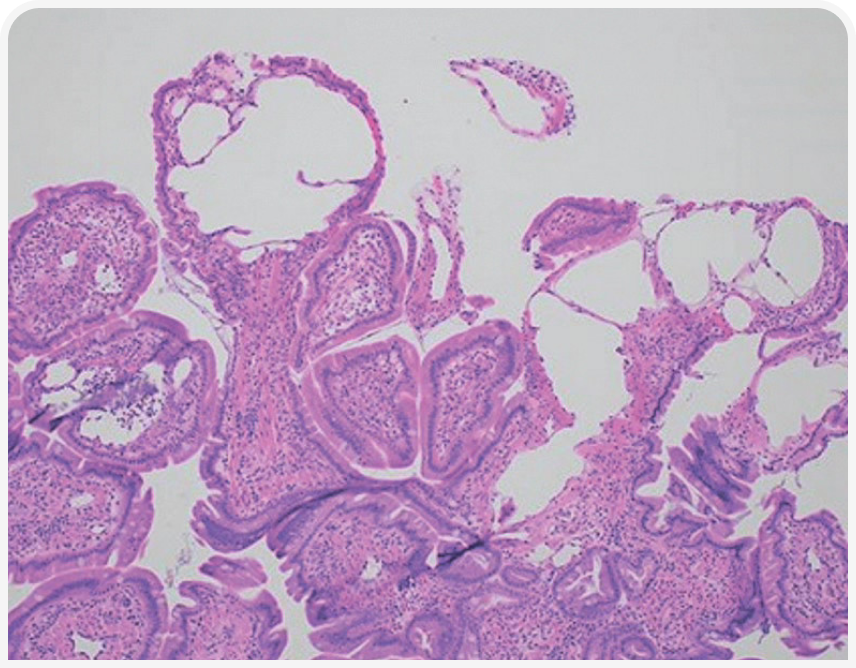

Чаще всего ЭПБ у собак обусловлена хронической воспалительной энтеропатией и лимфангиэктазией кишечника.